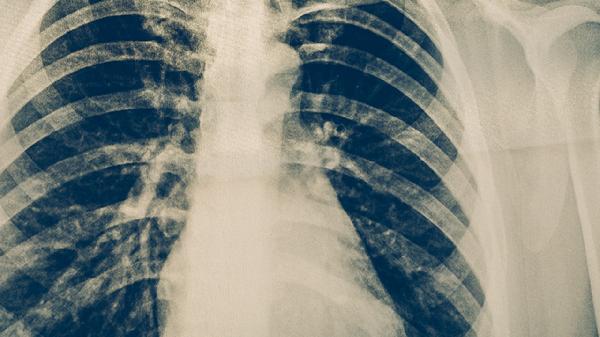

吸入性肺炎的表现主要有咳嗽、发热、呼吸急促、胸痛等。症状按早期表现到终末期发展,可能伴随痰液增多、呼吸困难、发绀等。